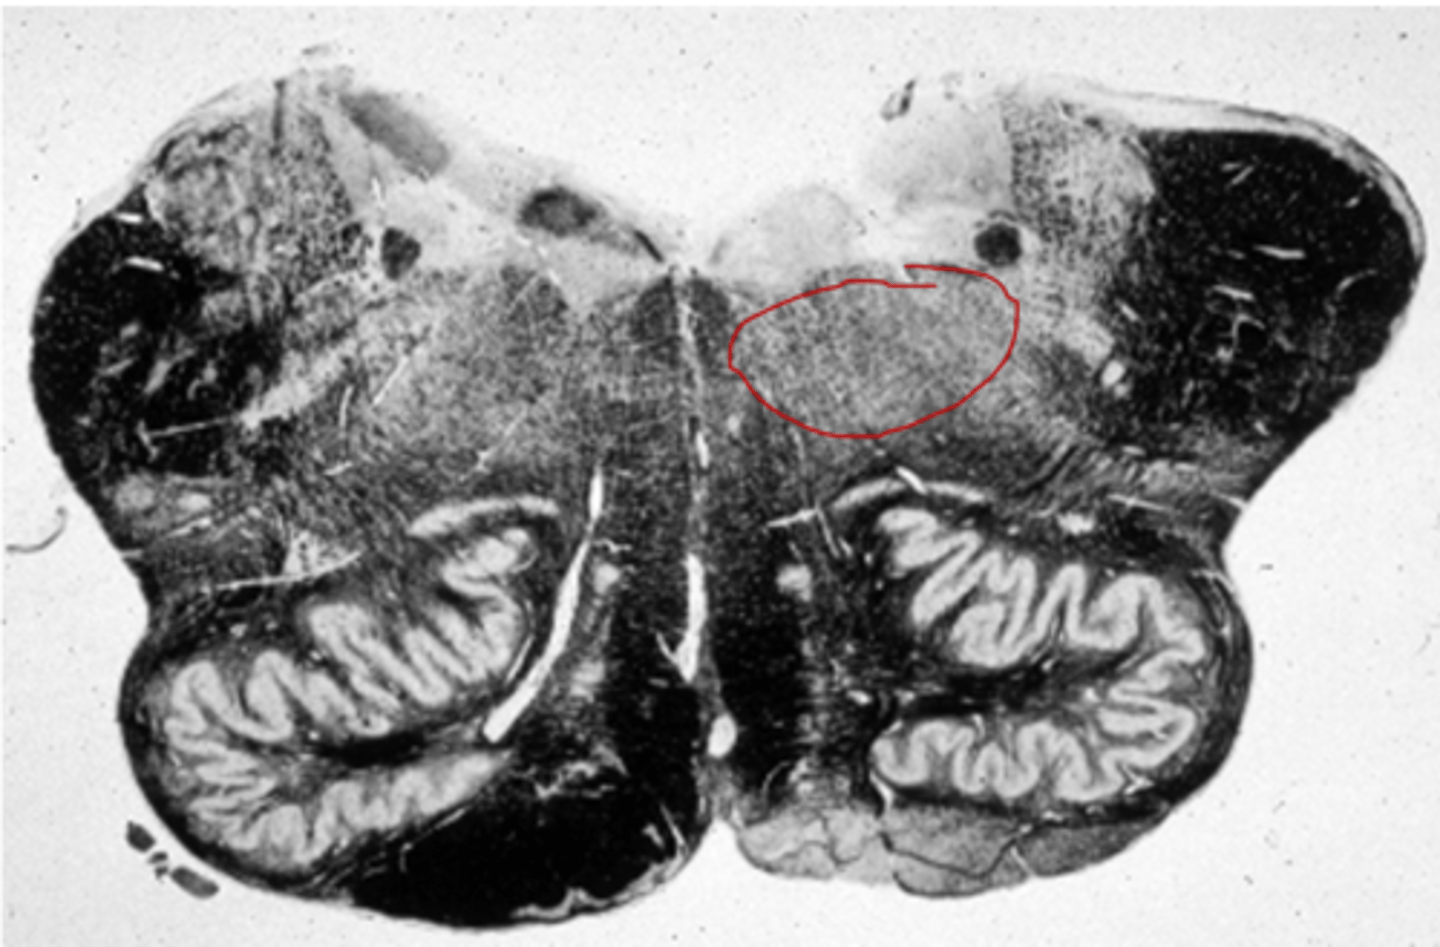

Substantia nigra

-Motor center that relays inhibitory signals to thalamus and basal nuclei preventing unwanted body movement

-Black nucleus pigmented with melanin

Substantia nigra senescence

-Degeneration of neurons leads to tremors of Parkinson disease

Cerebral peduncles midbrain

-Two anterior midbrain stalks that anchor the cerebrum to the midbrain

-Each peduncle has three parts

=Tegmentum, substantia nigra, other (not important)

Tegmentum

-Dominated by red nucleus

-Pink color due to high density of blood vessels

-Connections go to and from cerebellum for motor controls